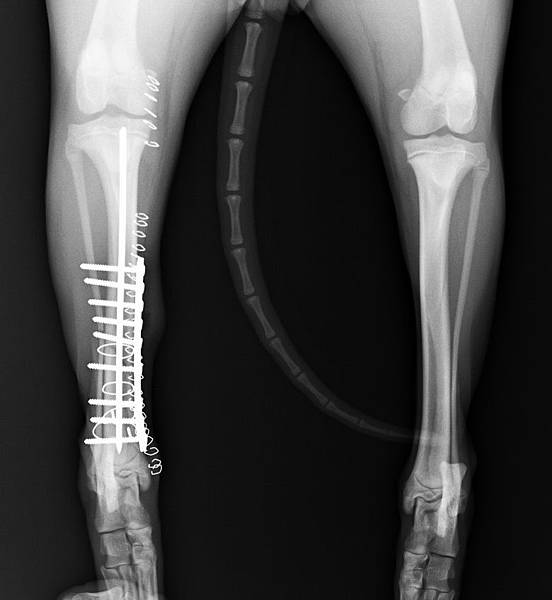

上圖為手術前X光: 小腿骨折的很誇張

1.jpg

2.jpg